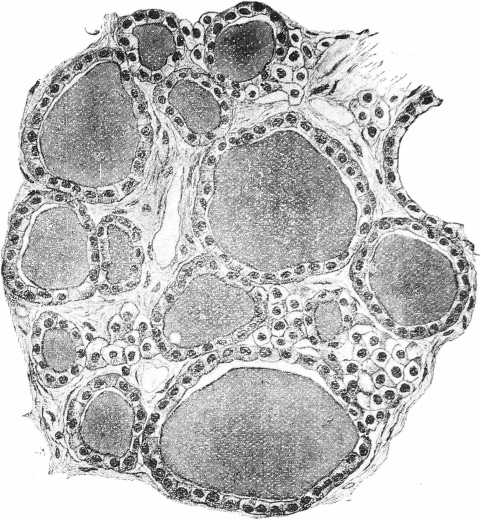

Наибольшія измѣненія въ щитовидной железѣ наступали подъ вліяніемъ тиреолитической сыворотки и адреналина, при чемъ подъ вліяніемъ этихъ агентовъ они развивались не съ одинаковой быстротой и не съ одной и той же интенсивностью. Скорѣе всего измѣненія щитовидной железы обнаруживались въ опытахъ съ тиреолитической сывороткой. Въ одномъ рядѣ случаевъ ихъ можно было наблюдать уже спустя 1 часъ послѣ впрыскиванія въ v. jugubaris 30 куб. цен. сыворотки. Въ это время удавалось констатировать умѣренное расширеніе сосудовъ, появленіе значительнаго количества большихъ эпителіальныхъ клѣтокъ въ стѣвкахъ фолликуловъ съ свѣтлой протоплазмой. Еще болѣе рѣзкія измѣненія приходилось встрѣчать при изслѣдованіи железы черезъ 6—24 часа (см. табл. II. рис. 3) послѣ впрыскиванія тиреолитической сыворотки. Протоплазма железистыхъ клѣтокъ представляется крайне набухшей, разрыхленной и пронизанной вакуолями, нѣкоторыя клѣтки превращались прямо въ сѣтку, въ которой виднѣлись довольно хорошо сохранившіяся ядра. Количество коллоидныхъ клѣтокъ въ одномъ рядѣ случаевъ казалось увеличеннымъ въ числѣ, въ другомъ оставалось въ предѣлахъ нормы. Величина фолликуловъ и степень растяженія ихъ коллоидомъ непостоянно, также постоянно измѣненіе калибра кровеносныхъ сосудовъ, непредставляющихся то болѣе, то менѣе широкими. Дальнѣйшія измѣненія щитовидной железы, насколько позволяютъ судить наши препараты, сводятся къ постепенному возвращенію органа къ нормальному состоянію. Протоплазма славныхъ железистыхъ клѣтокъ принимаетъ вновь зернистый видъ. Вакуоли занимаютъ только небольшую частъ клѣтки. Этотъ процессъ возстановленія обычной структуры клѣточнаго тѣла происходитъ въ однихъ случаяхъ довольно быстро, такъ что по истеченіи уже 24 часовъ щитовидной железѣ наблюдается картина, почти соотвѣт ствующая уже той, которая встрѣчалась у нормальныхъ животныхъ. (См. табл. III. рис. 5). Въ другихъ случаяхъ тотъ же процессъ идетъ гораздо медленнѣе и по истеченіи 48 часовъ на препаратахъ изъ щитовидной железы можно было встрѣтить еще глубокія измѣненія строенія въ фолликулахъ съ преобладаніемъ сильно разбухшихъ, безцвѣтныхъ, лишенныхъ нормальной зернистости протоплазмы клѣтокъ, ядра которыхъ частью были смѣщены и окрашивались диффузно. (См. табл. II, рис. 4).

Измѣненія въ щитовидной железѣ у животныхъ, подвергавшихся многократнымъ впрыскиваніямъ адреналина (въ постепенно возрастающихъ дозахъ, начиная отъ 0,04—1,6 mgrm. для кролика и 0,4—5,0 mgrm. для кошки) являются дальнѣйшимъ развитіемъ только что описанныхъ. Щитовидныя железы въ большинствѣ случаевъ представляются уменьшенными. Эпителіальныя клѣтки фолликуловъ однихъ случаяхъ высока, съ протоплазмой въ состояніи разрѣженія. Въ нѣкоторыхъ клѣткахъ случалось видѣть большія глыбки коллоиднаго вещества. Ядра были смѣщены къ просвѣту фолликуловъ. (См. табл. 1, рис. 2). Въ другихъ случаяхъ эпителій фолликуловъ очень низкій, съ плохо различимой зернистой протоплазмой, съ вытянутыми ядрами. Соединительная ткань мѣстами увеличена. (См. табл. 111, рис 6). Измѣненія этого типа говорятъ о наступленіи глубокаго функціональнаго истощенія. О состояніи истощенія можно вывести заключеніе также на основаніи прекращенія у нѣкоторыхъ нашихъ животныхъ гликозуріи, которая въ началѣ каждаго наблюденія у такихъ животныхъ наступала послѣ впрыскиваній адреналина, что можетъ быть сопоставлено съ аналогичнымъ наблюденіемъ Eppinger'a, Falta и Rudinger’a надъ дѣйствіемъ адреналина на животныхъ, лишенныхъ щитовидной железы.

Рис. 4. Срѣзъ изъ щитовидной железы кошки спустя 48 часовъ послѣ впрыскиванія тиреолитическій сыворотки. Фиксація въ 10% формалинѣ, окраска гематоксилиномъ и эозиномъ Увеличеніе: Leitz. Ocular 4, Object. 6.

Рис. 6. Срѣзъ изъ щитовидной железы кролика послѣ многократныхъ впрыскиваній адреналина. Фиксація въ 10% формалинѣ, окраска по van-Gieson’y. Увеличеніе: Loitz. Ocular 1, Object. 7.